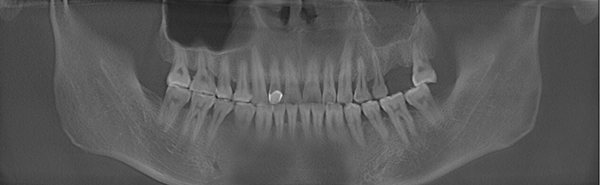

郑先生口腔全景ct拍摄

郑先生口腔内部全景片

种牙成功后的郑先生口腔ct全景